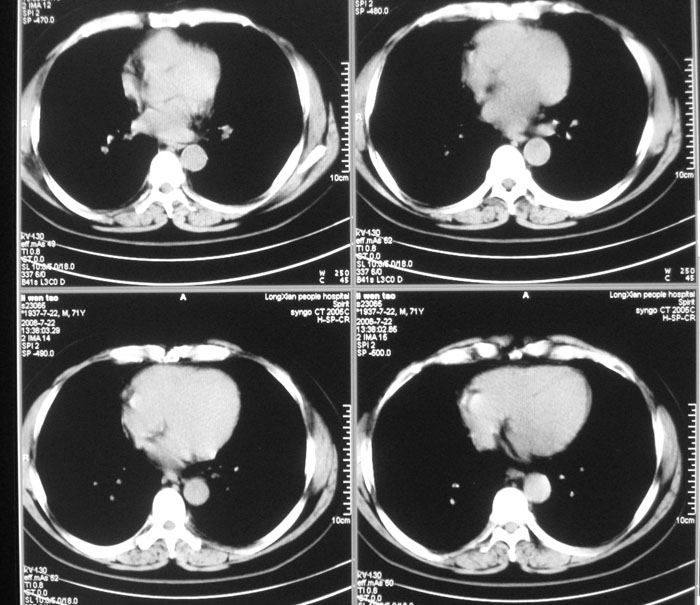

以下是引用wwwwtyy在2008-7-27 17:46:00的发言:[br]中心型肺癌不除外

以下是引用子十在2008-7-27 17:49:00的发言:[br]考虑中心性肺癌

以下是引用光影★笑子在2008-7-27 19:39:00的发言:[br]建议:行支气管镜检查排除肺癌。

以下是引用晓杰在2008-7-27 19:20:00的发言:[br]支持楼主意见;中心型肺癌不除外。

以下是引用zhangjixiang在2008-8-6 20:02:00的发言:[br]右主支气管明显变窄伴右上叶尖段不张,结合年龄,考虑右侧中央型肺癌可能性大,纤支镜检可确诊.